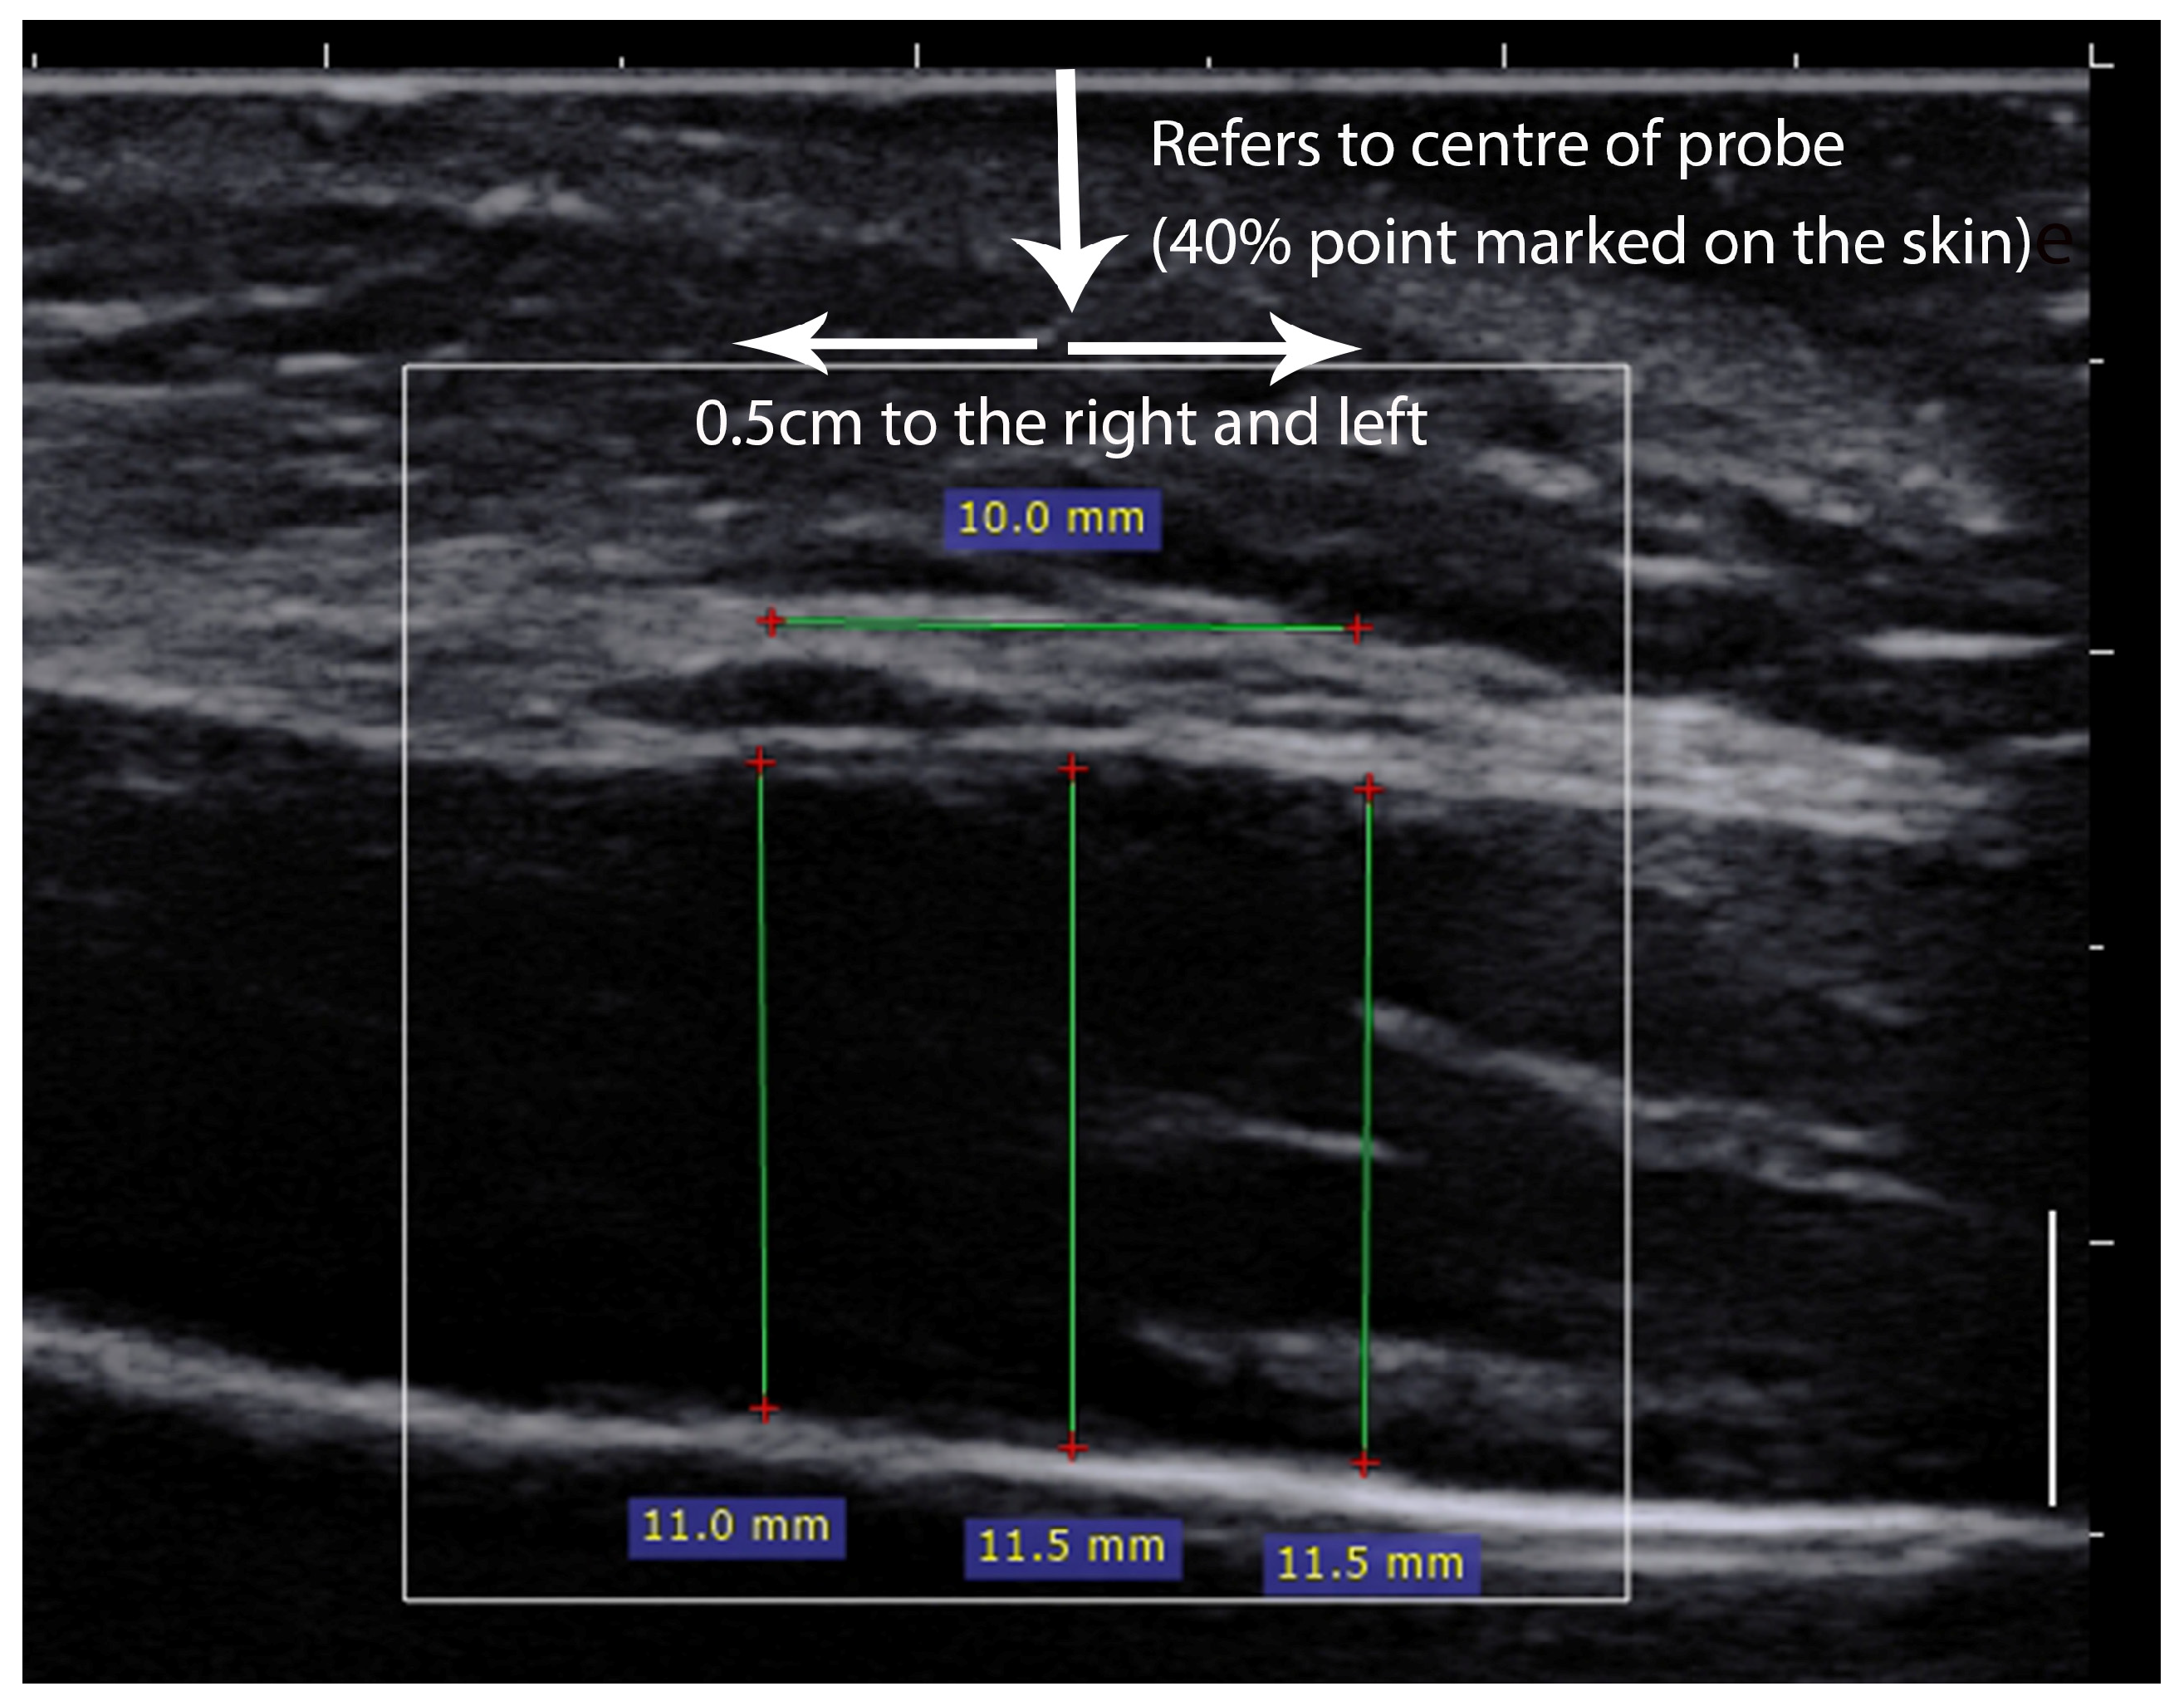

2.3. Ultrasound Measurements

2.5.1. Ultrasound Parameters